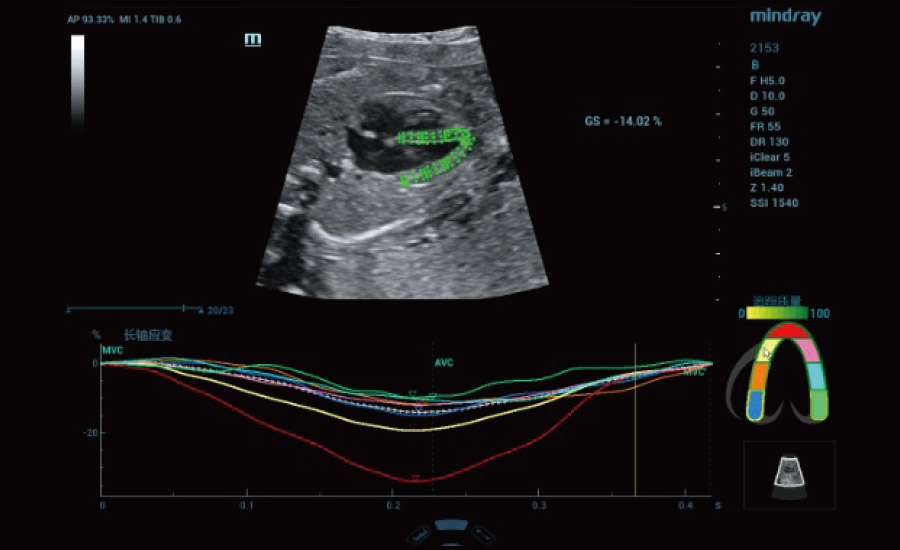

Scenario-oriented Full-stack Intelligence

Combining advanced algorithms and domain-specific knowledge, the innovative Smart Scene solution enables auto identification of tissue characteristics and provides organ-specific diagnosis with full-stack intelligence. Based on auto scenario identification, the solution not only realizes smart 2D scanning with auto settings and measurements, but also delivers 3D full-stack intelligence in every step from volume imaging optimization to the difficult 2D plane acquisition, and quantification throughout whole procedure. It helps a lot in reducing the dependency on clinical skills, while increasing diagnostic accuracy, confidence and efficiency.

Professional Ultrasound Solutions with Full-stack Intelligence

Fertility

Obstetrics

Gynecology

Urogynecology